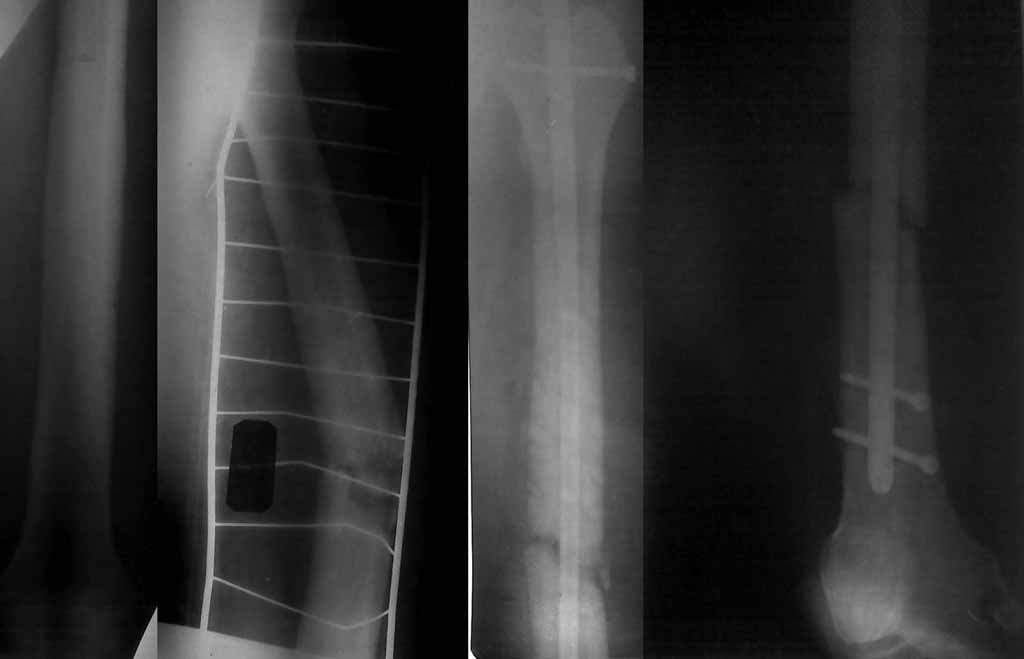

26 марта при незначительной травме - поперечный перелом бедра в месте трепанации.

Выполнена закрытая репозиция БИОС с первичной динамизацией. Ходит с дозированной нагрузкой на левую ногу.

Здравствуйте, коллеги. Досылаю рентгенограммы, качество низкое, извините.